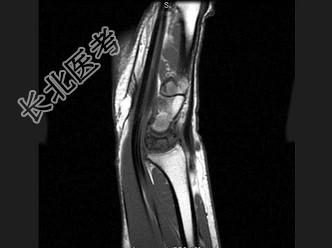

- 单项选择题女,41岁, 纺织工,腕部疼痛无力数周, 结合CR和MR,最可能的诊断是 ( )

B、月骨缺血坏死